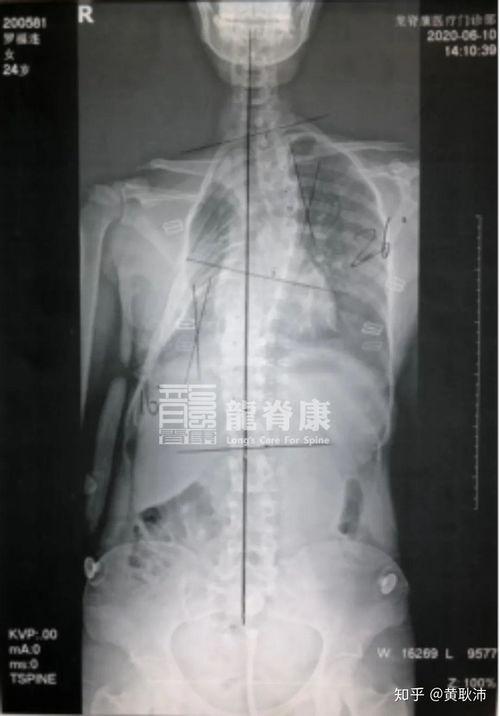

五、成人胸廓畸形的诊断

1. 体格检查:医生会通过观察和触摸来初步判断。

2. 影像学检查:比如X光、CT等,可以更清楚地看到胸廓的形状。